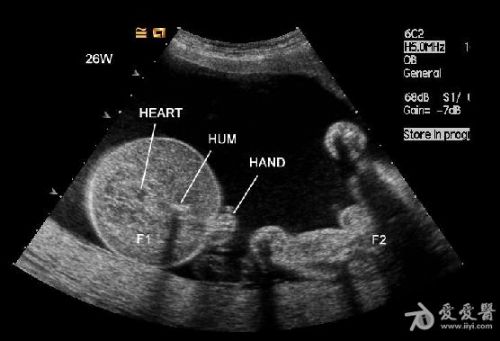

是双胎,其中畸形的那个明显没有上半身及头部,只有下半身和一点点短小的左上肢。

1、双胎中一胎形态、结构发育正常,另一胎出现严重畸形,以上部身体严重畸形为主,可有下部身体如双下肢等结构。

3、上部身体严重畸形,可表现为无头、无双上肢、胸腔发育极差。